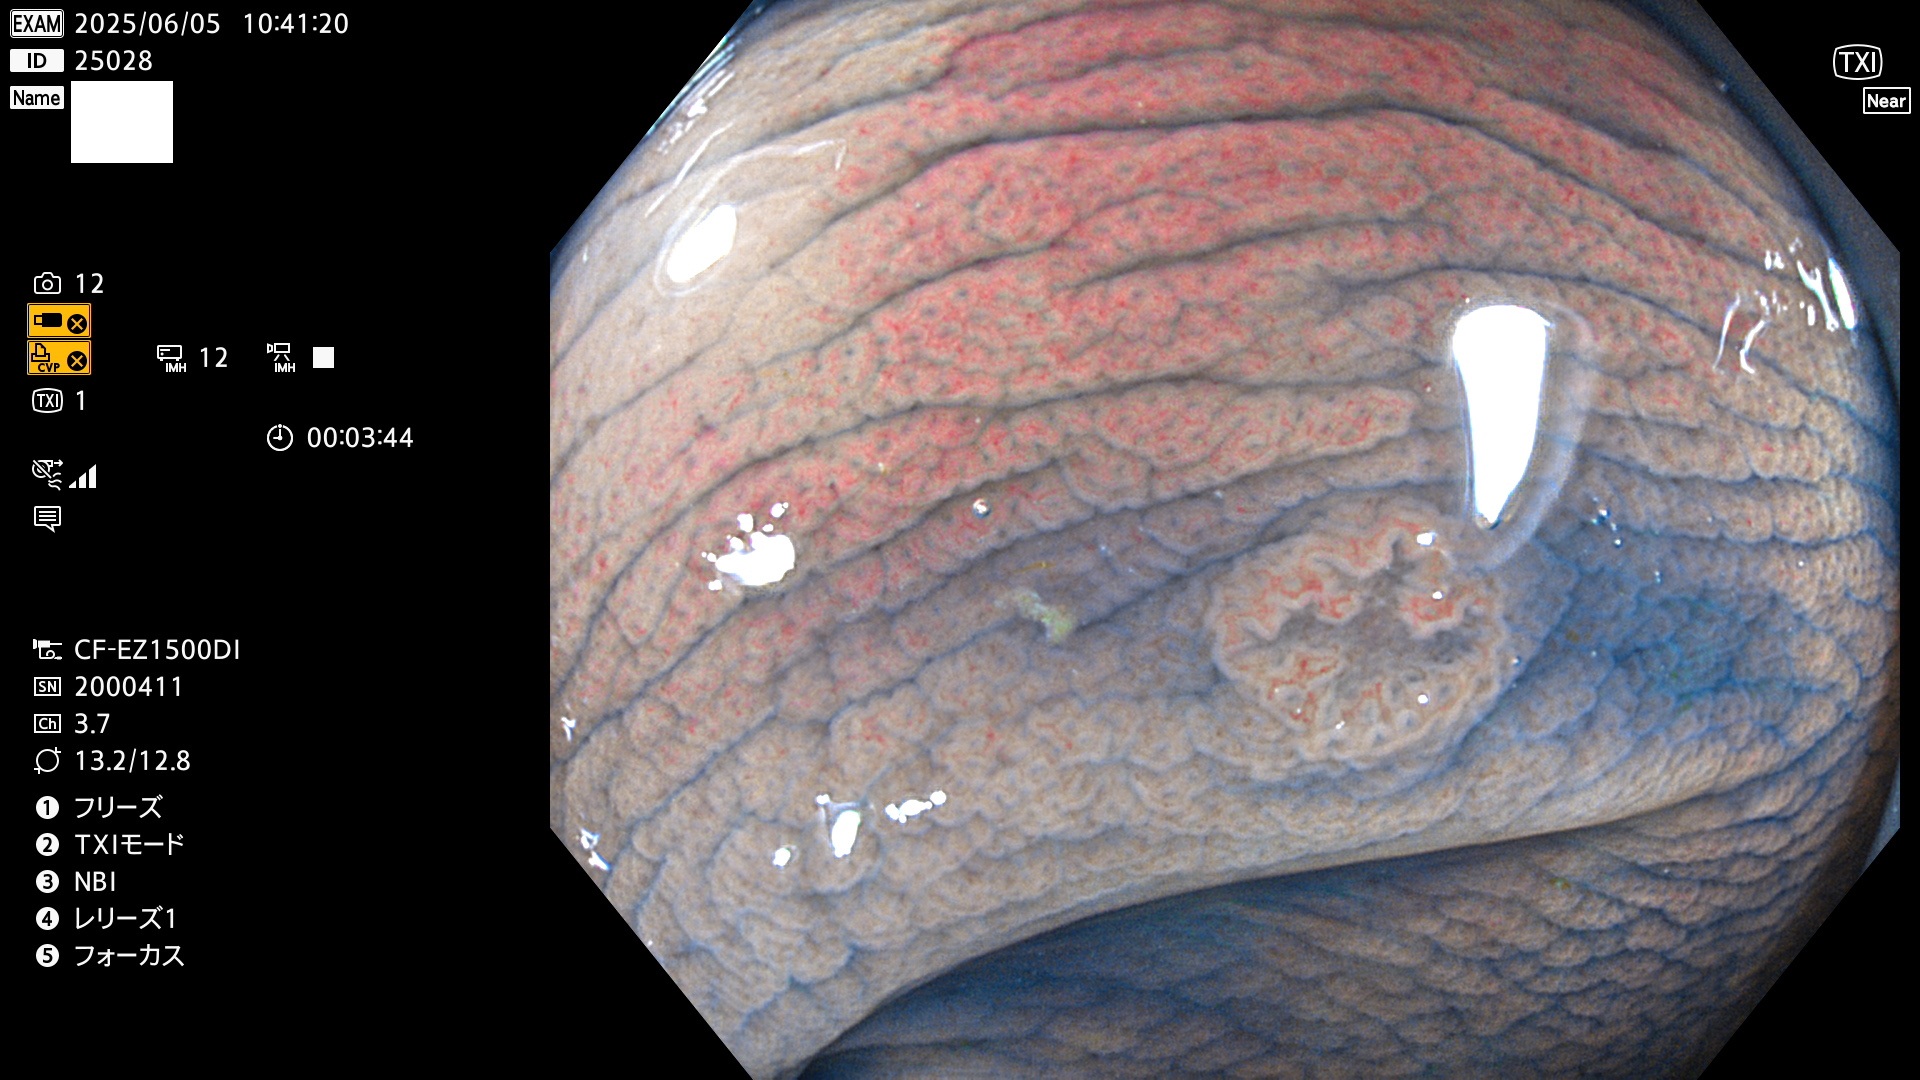

抽出の対象期間 2025年6月5日〜6月8日の4日間(48件の検査)4個 (4/48=8%)